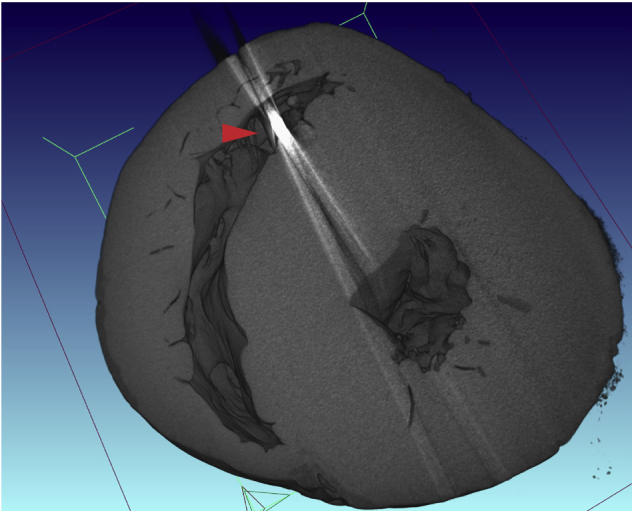

Figure 5.

A μCT of the explanted heart in short-axis view showing biventricular hypertrophy and foreign material in the right ventricle corresponding to a right ventricular ICD lead (red arrow).